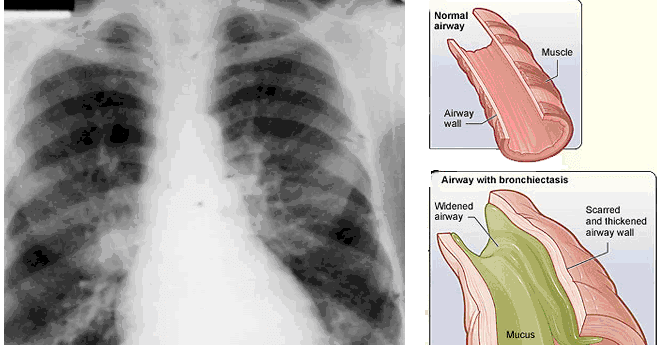

Cough Ncp For Copd : Chronic bronchitis consists of a long term cough with mucus.